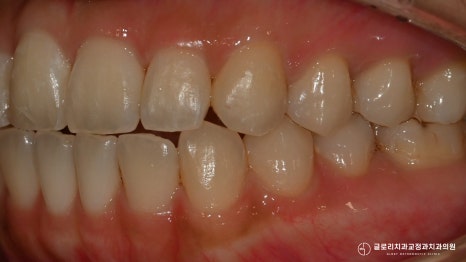

틀어진 앞니가 제자리를 찾아 배열되었으며

전체적으로 봤을 때 훨씬 긴밀하고

고르게 바뀐 것을 확인할 수 있었습니다.

『악궁도 둥근 형태로 더 예뻐진 모습이죠?』

고정식 유지 장치를 부착하여

틀어짐, 이동을 막아드리며

망우동치과 의 모든 과정을 마칠 수 있었습니다.